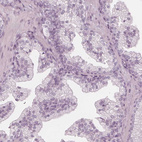

Immunohistochemistry analysis in human endometrium and prostate tissues using HPA029473 antibody. Corresponding PAEP RNA-seq data are presented for the same tissues.